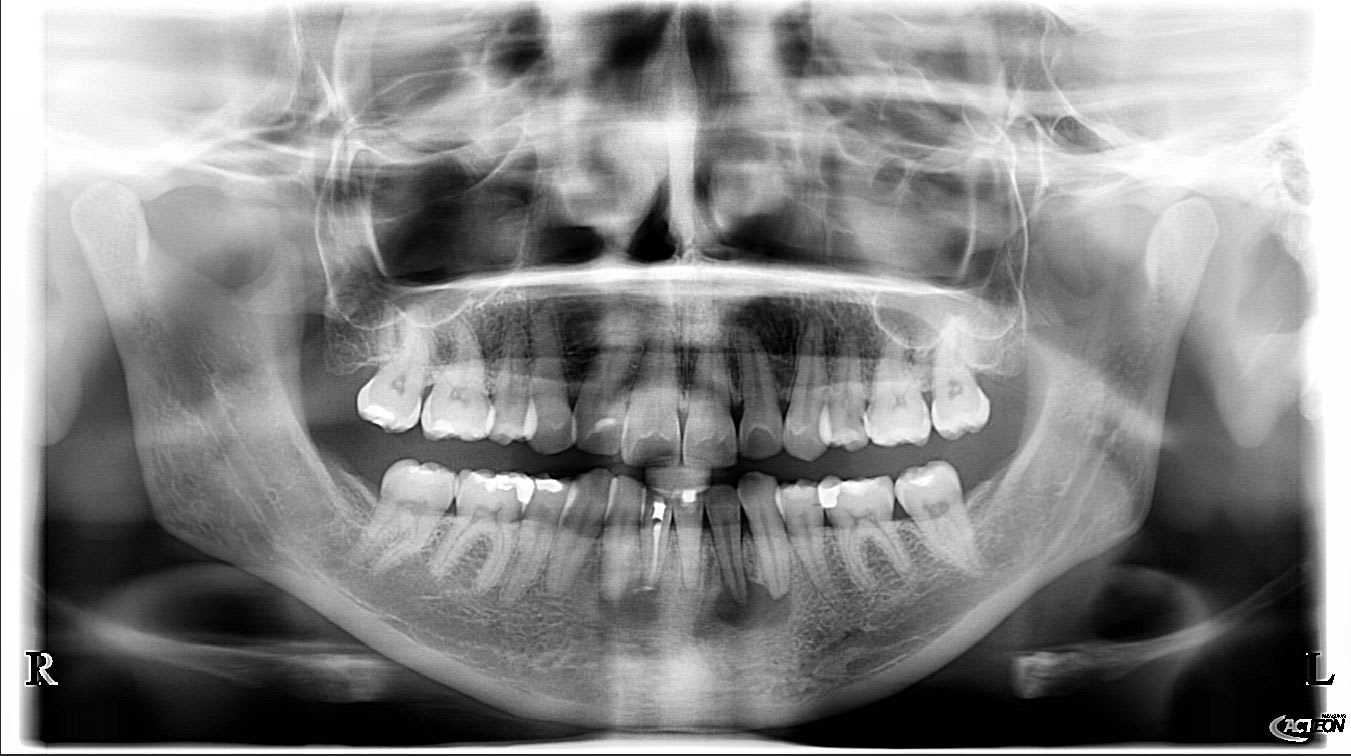

Patiente sans douleur avec decouverte fortuite de deux images radioclaire sur le secteur anterieur mandibulaire à la 1ere consultation

Test vitalité negatif sur 41 et 32

Test vitalité positif sur les autres

Mais ce qui m'interpelle c'est le test positif sur la 31 , mais il est ou son canal et quel est la teinte de cette dent sans patate apicale ? ;o))

Donc effectivement test negatif sur 41 31 32

D'apres ton cbct, Il me semble que t'as zappé un deuxième canal (en lingual) sur cette 41.

D'ailleurs on l'aurait deviné même sans réaliser le cbct par une bonne analyse de ta rétro-alvéolaire.

la 31 présente aussi une lésion apicale, et une oblitération de l'espace pulpaire, si tu n'es pas serein (ne), adresse ta patiente à un endo exclusif

Attention, la 32 pourrait aussi avoir 2 canaux (type 2 de weine)

Et n'oublie pas les caries en distal de 15, 25, 26 et 35

une rétroalvéolaire de 12 serait aussi intéressante à étudier (artéfact ?)